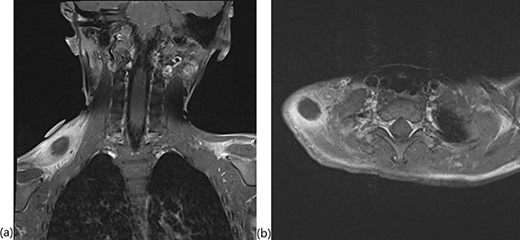

A 4-year, 7-month-old male presented to our otolaryngology department with supraclavicular fullness and an enlarging, firm, right-sided 2 × 3-cm neck mass. At the initial visit, his vital signs were remarkable for an isolated fever of 101.6°F. A pertinent review of systems was negative per the patient’s parents. Possible environmental exposures included mice and bats as the patient lived on a farm. Past medical history was unremarkable. Physical examination demonstrated a mass located on the superior dorsal side of the right shoulder with a few mildly enlarged, mobile and cervical lymph nodes. An ultrasound of the mass was negative for abscess. The patient was started on ampicillin and sulbactam due to concern for infection; however, a pharyngeal swab and chest radiograph were negative. A magnetic resonance imaging (MRI) demonstrated the mass within the mid-belly of the right trapezius muscle and revealed significant inflammation and cellulitis of the subcutaneous tissue, as well as a small fluid collection in the supraclavicular space consistent with necrosis (Fig. 1). A computed tomography (CT)-guided core biopsy was then performed. Gram stain, cultures and polymerase chain reaction diagnostics were all negative. Extensive necrosis in the biopsy prevented adequate pathologic evaluation.

T1-weighted MRI with fat saturation showing the intramuscular mass in the (a) coronal and (b) axial planes.